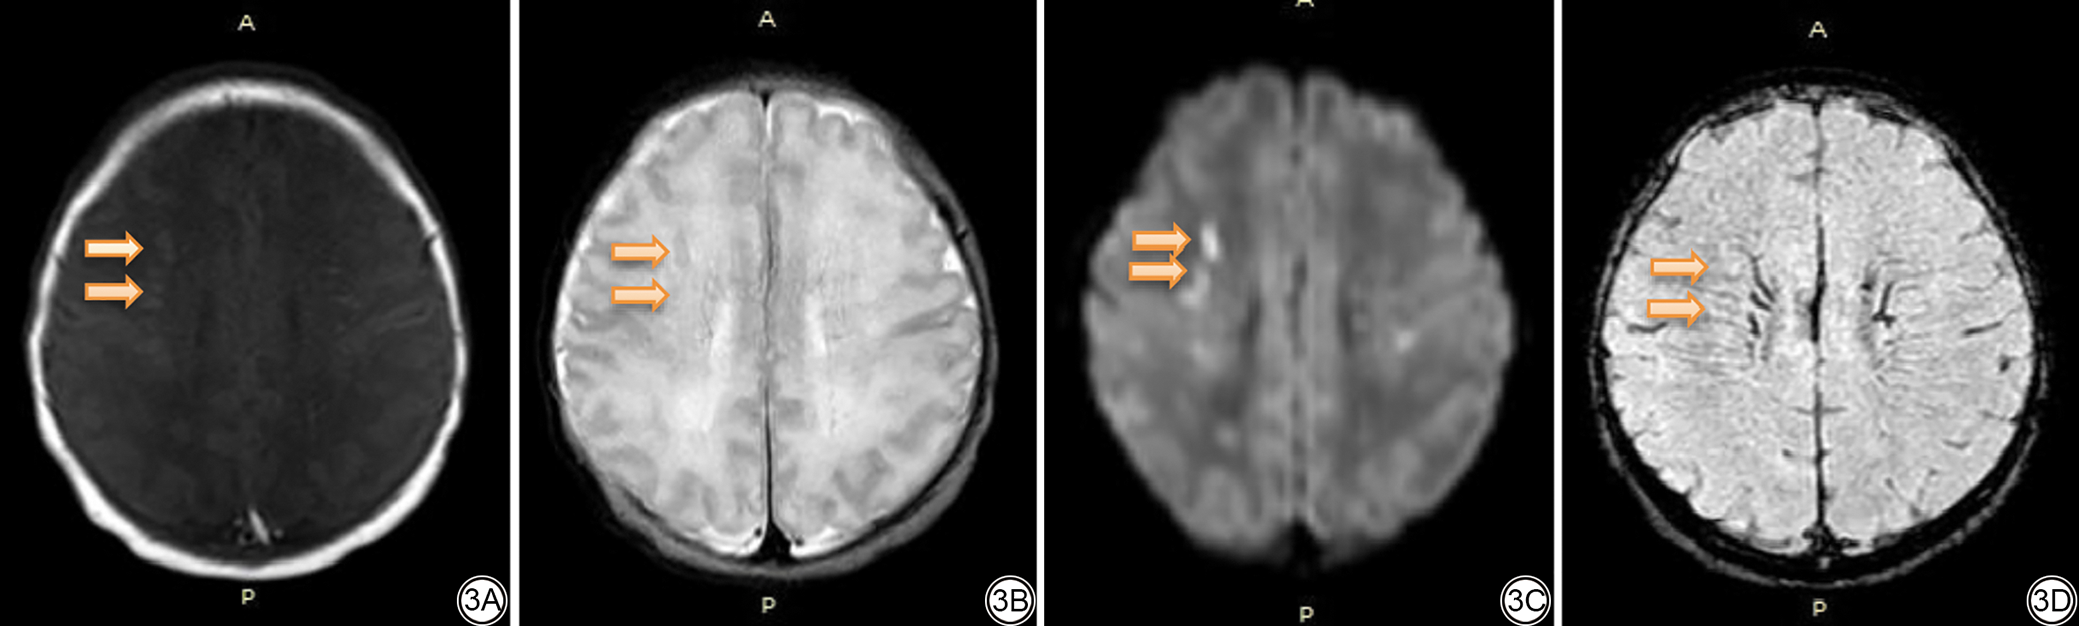

图1  女,胎龄40+1周,宫内窘迫。1A:在T1WI上双侧小脑半球未见明显异常信号;1B:在T2WI上右侧小脑半球可见点状低信号出血影;1C:在DWI上右侧小脑半球可见低信号;1D:在SWI上双侧小脑半球可见多发点状低信号出血影。T1WI:T1加权成像;T2WI:T2加权成像;DWI:扩散加权成像;SWI:磁敏感加权成像。

Fig. 1  Scans of a female (gestational age = 40+1 weeks) with intrauterine distress. 1A: No obvious abnormal signal was found in the bilateral cerebellar hemispheres on T1WI; 1B: On T2WI, a punctate low-signal shadow was found in the right cerebellar hemisphere; 1C: A low signal was detected in the right cerebellar hemisphere by DWI; 1D: Multiple punctate low-signal shadows were found in the bilateral cerebellar hemispheres by SWI. T1WI: T1-weighted images; T2WI: T2-weighted images; DWI: diffusion-weighted imaging; SWI: susceptibility-weighted imaging.